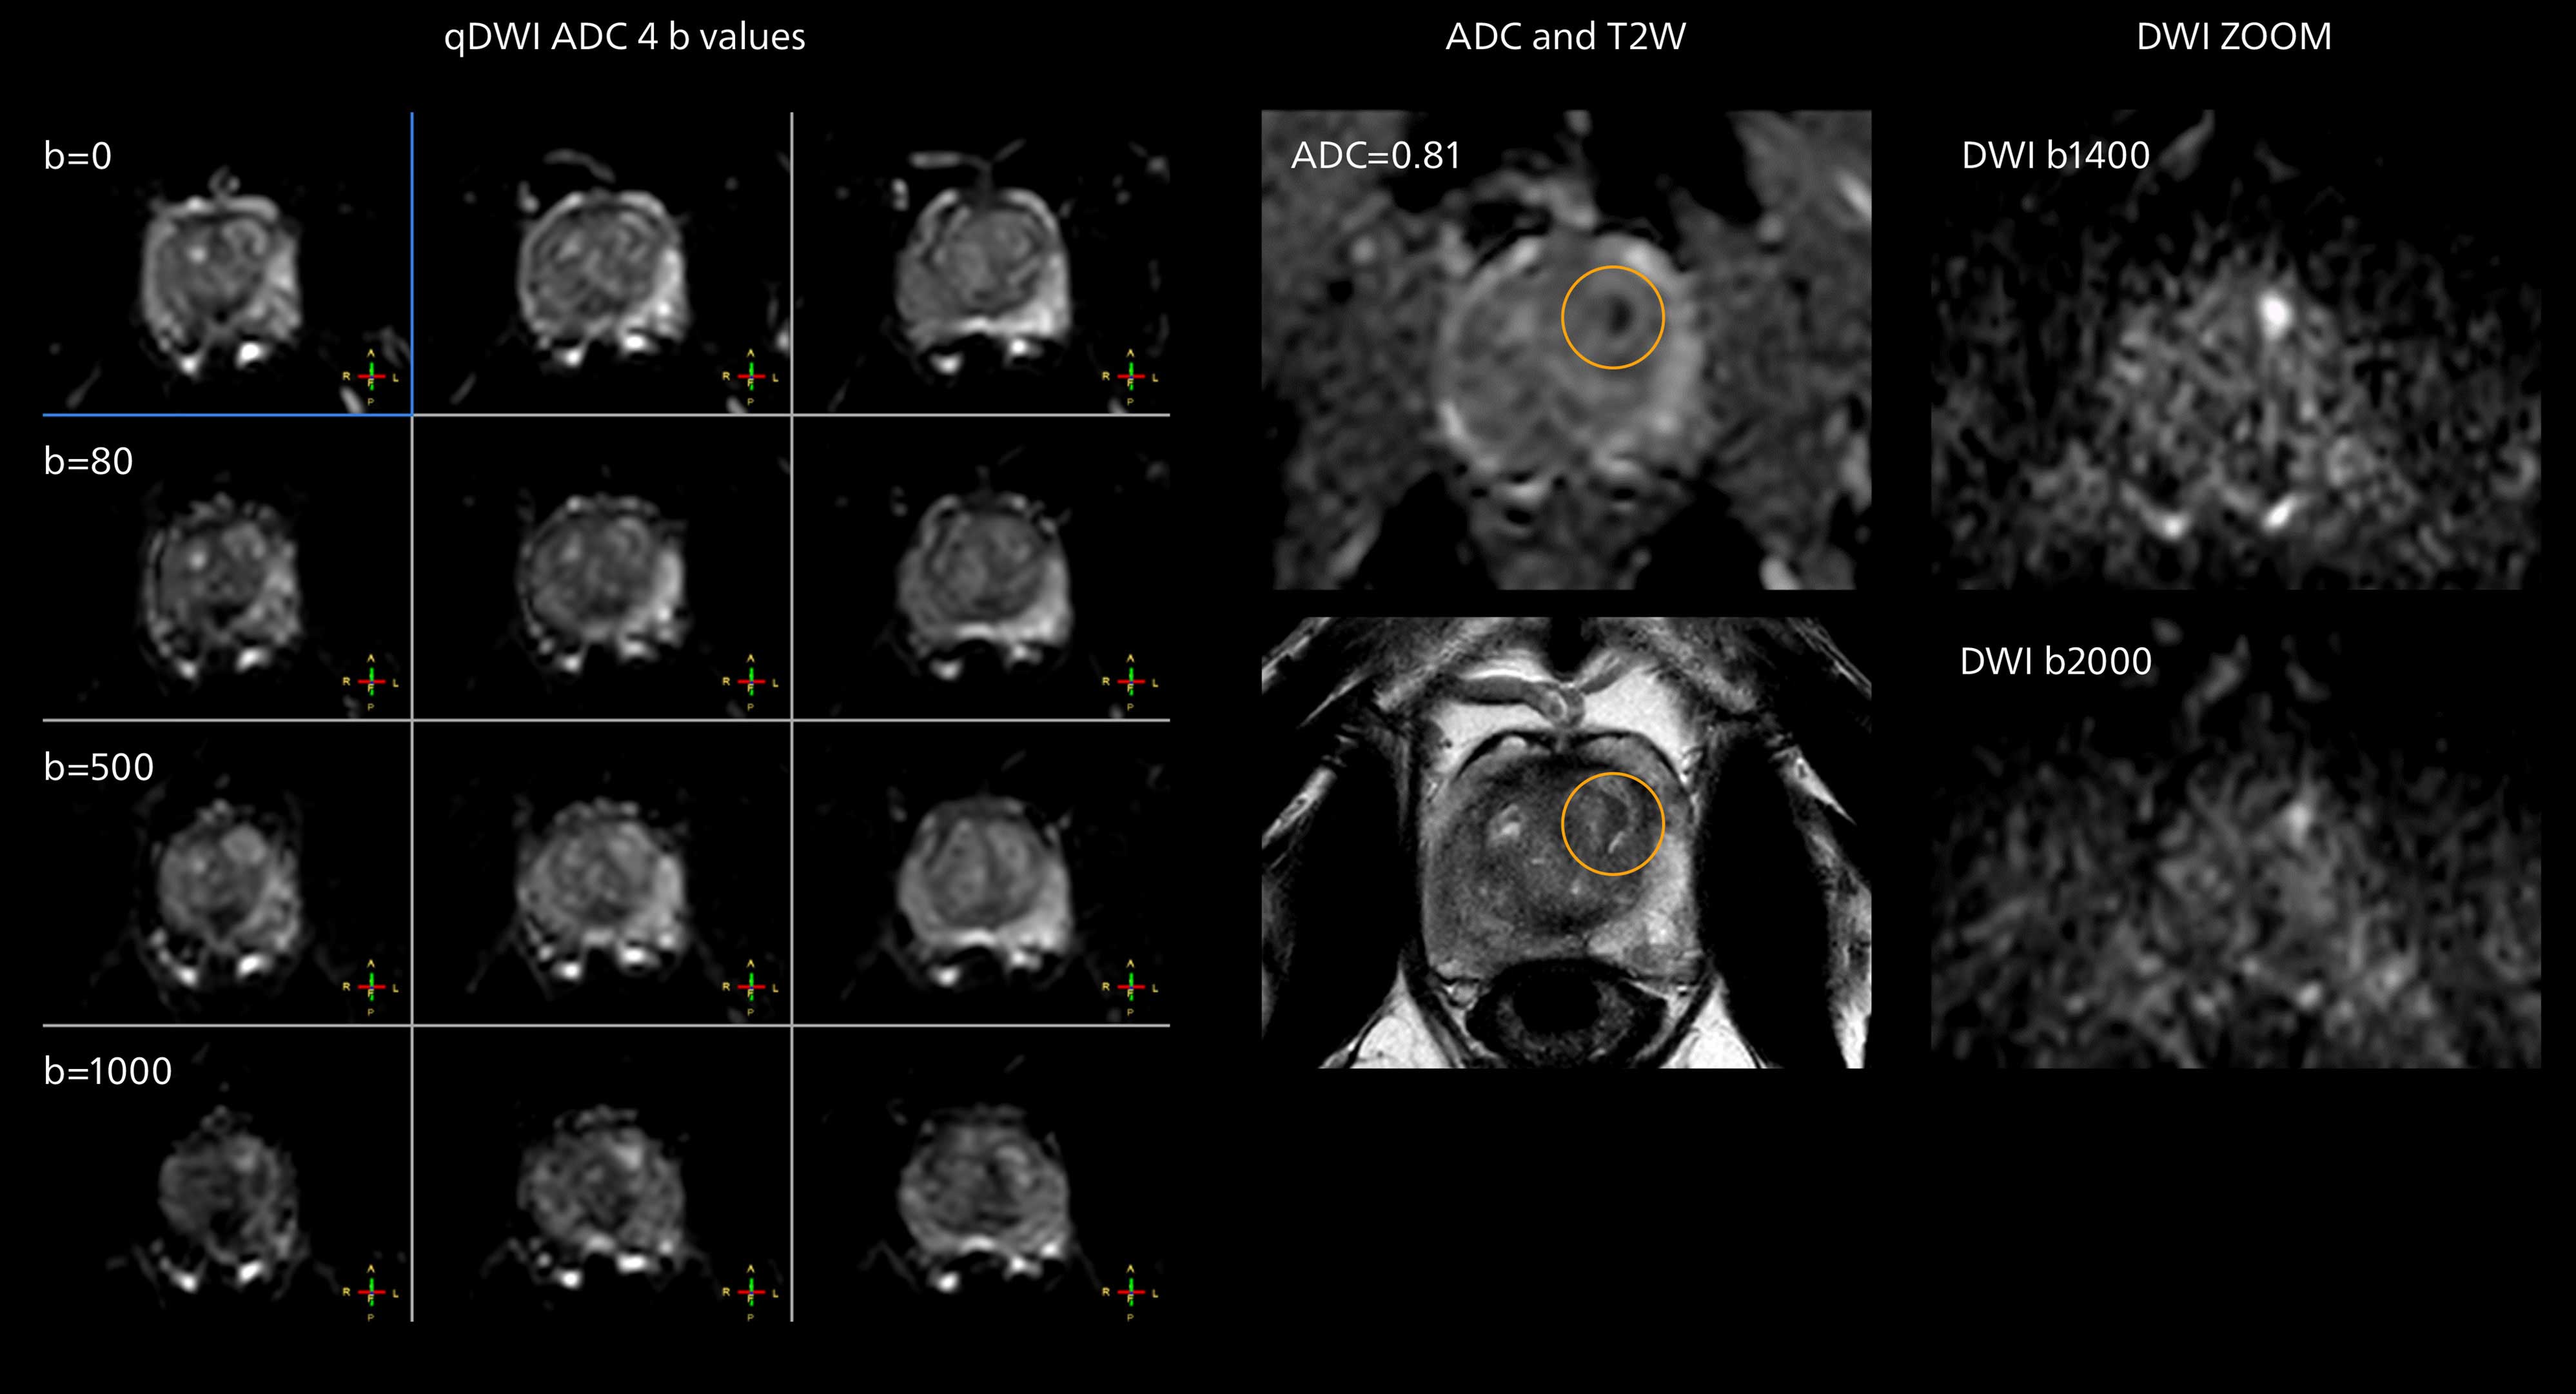

Diffusion weighted imaging of prostate

The examples on the left show the regular clinical diffusion protocol with four b-values up to b1000 s/mm². On the right, the T2W image shows a hypointense lesion that has low ADC and is clearly visible in b1400 and b2000 diffusion images, suggesting malignancy.